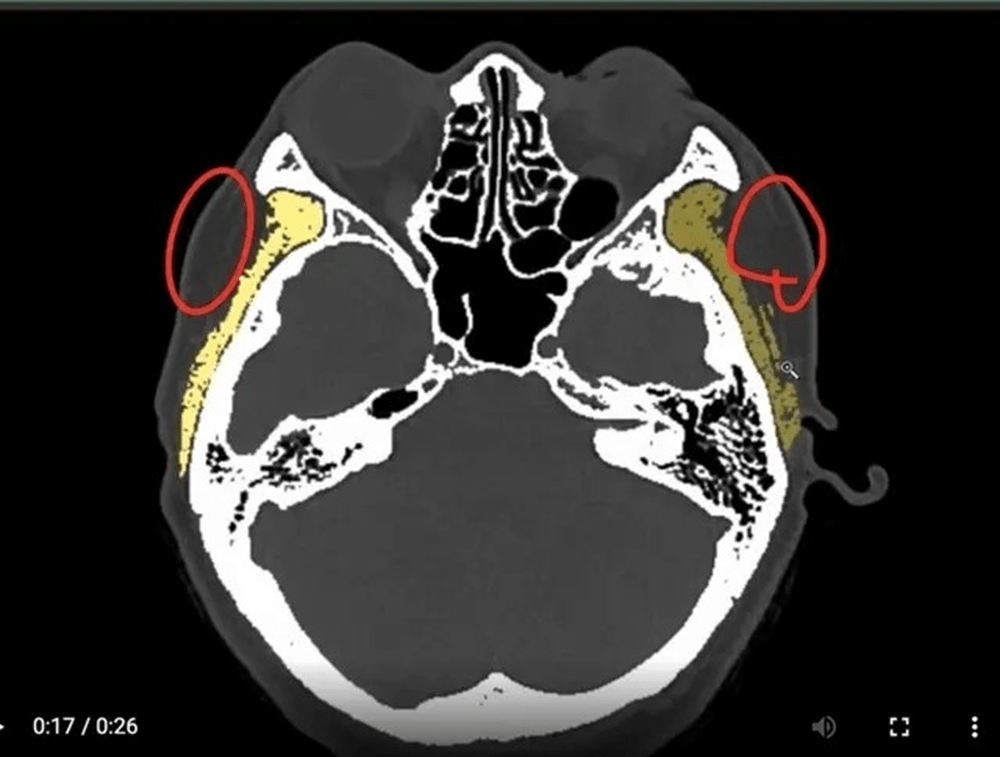

電腦斷層發現:下圖為墊片位置穩定平順(紅色箭頭),下下圖紅圈處為注射脂肪下移與吸收不均的腫塊。為李醫師客製化墊片手術後兩年半長期和太陽穴注射填充結果比較:

Filler/ fat augmentation is quite different from the implant sheet on temple area. Long term results show on 3D CT scan, we can find the filled temple disfigured a lot compared with the implant sheet on temple contour.

範例 二:淺藍色為墊片(黃色為肌肉部分)

上圖:在3D電腦斷層掃描顯像:微創墊片在太陽穴(近三年)和注射填充的效果對比

紅色箭頭腫塊為填充物。容易形成饅化大頭感。